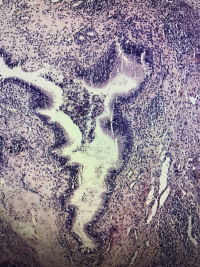

鼻息肉

性别

女

年龄

27

临床诊断

一般病史

鼻窦炎

标本名称

大体所见

灰白碎组织,大小3.2✖️2.4✖️0.5cm,部分成囊状

图1

鼻粘膜息肉。